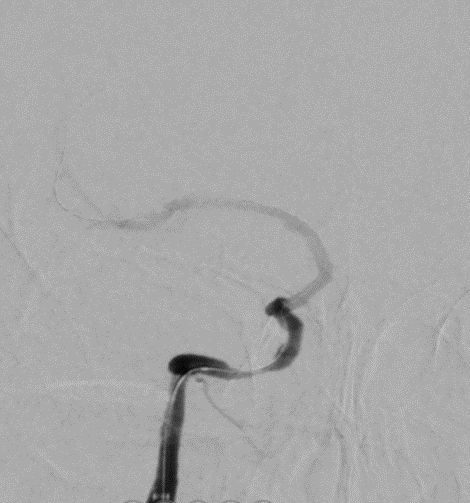

扩张后造影。

导丝怎么扩【载药时代 球扩天下】NOVA DES®颅内药物洗脱支架在颈内动脉颅内段重度狭窄的应用二例!_https://www.jmylbn.com_新闻资讯_第30张

支架通过病变。

导丝怎么扩【载药时代 球扩天下】NOVA DES®颅内药物洗脱支架在颈内动脉颅内段重度狭窄的应用二例!_https://www.jmylbn.com_新闻资讯_第31张